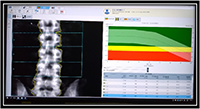

骨密度

骨密度測定

腰椎と股関節にて骨密度の測定を行うため、

より正確に骨密度の測定ができます。

再度検査する際は以前の結果があるため再現性良く検査が受けられます。

横になって検査が出来るので手足の悪い人も安心して検査が受けられます。

検査時間は腰椎と股関節を合わせても5分程度で被ばく線量も少なく安全です。

骨粗鬆症は年齢と共に骨の強度が弱まり骨折しやすくなる病気です。

骨密度検査は骨粗鬆症を診断する上で重要な検査です。